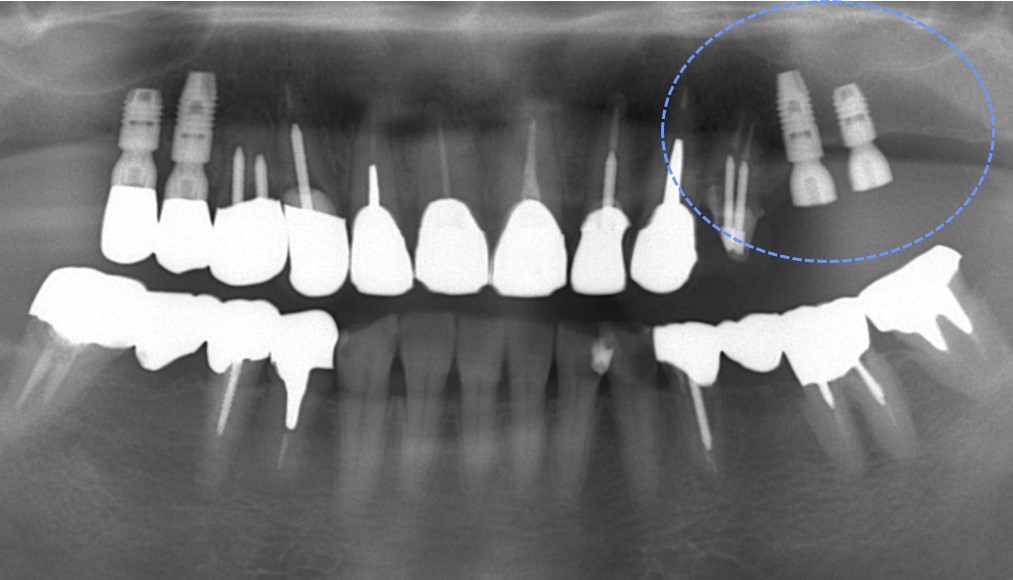

インプラント埋入直後の写真です。限られた骨幅にインプラントを埋入できています。

術後4年経過のレントゲン写真です。

インプラント周囲の骨も安定しており、良好に経過しています。

4年経過していますが今のところ良好に経過しています。予後が良好なことが最も重要なことと考えています。